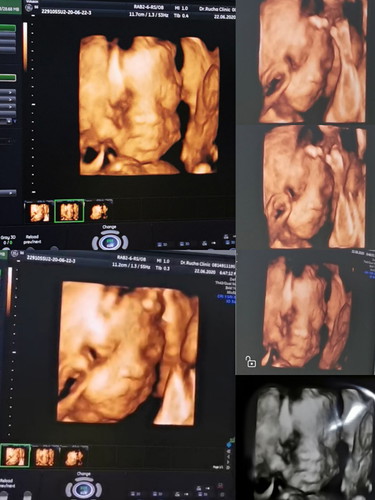

💕26w1d กำหนดคลอด 27ก.ย.ค่ะ💕

ทีมกันยายนเป็นยังไงกันบ้างคะ บ้านนี้ลูกชาย น้องน้ำหนัก 1,036 กรัมแล้วค่ะ นอนเอาเท้าพาดหน้าสองข้างโชว์ช้างน้อยเลย 5555😍